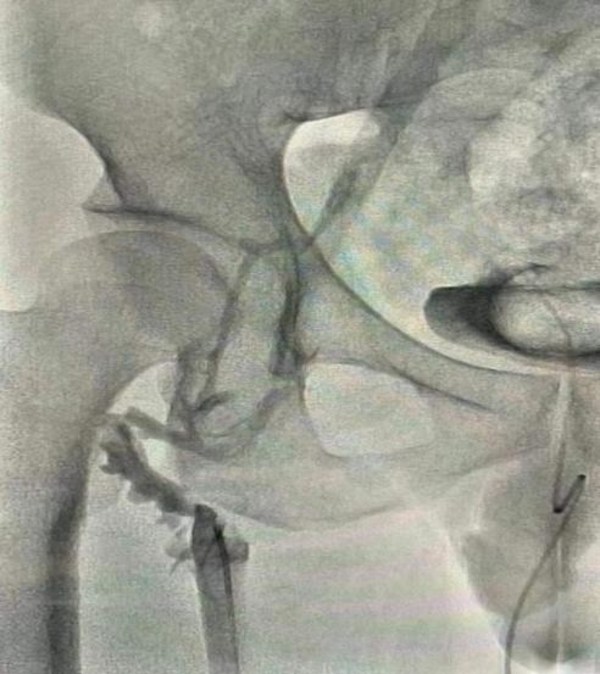

吸栓前造影顯示血栓栓塞

從同濟(jì)大學(xué)附屬第十人民醫(yī)院和同濟(jì)大學(xué)介入血管研究所了解到,患者是一名27歲的男性,因右下肢全程腫脹疼痛5天入院治療。經(jīng)超聲檢查后發(fā)現(xiàn)右下肢深靜脈處有血栓形成,位于股靜脈和髂靜脈之間,測量后得知血栓長度11*70mm,屬于靜脈急性血栓。